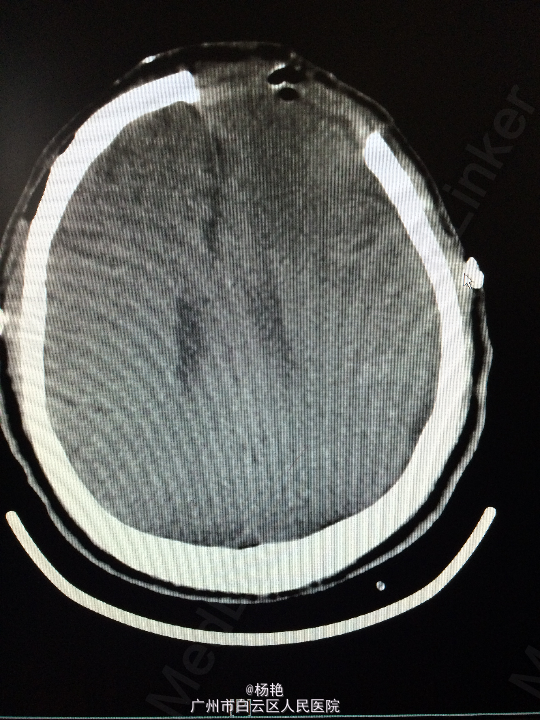

主诉:反复头痛2年加重1周 病史:患者诉两年前无明显诱因反复出现头晕头痛不适,近一周来症状加重,无恶心呕吐、无行走不稳、肢体乏力、意识障碍等。遂至当地医院诊治,行头颅CT、MR检查均提示颅内占位,良性可能性大,考虑脑膜瘤。今患者为求进一步治疗而入我院。

查体:神经系统查体未见明显异常 辅助检查:头颅MR提示:左侧额叶区域较大类圆形肿物,多考虑脑膜瘤可能;大脑前动脉及中动脉受压,中线偏移。

诊断:左额叶脑膜瘤 处理:在静脉全麻下行左侧额底脑膜瘤切除术,术后病理提示:脑膜瘤